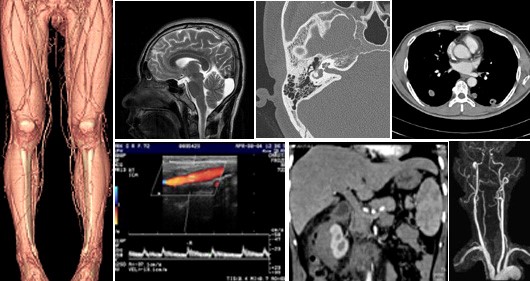

영상진단의 경우, 기존에 알려져 있는 X-선을 이용한 인체의 단순촬영 뿐만 아니라, 현대과학의 눈부신 발달에 힘입어, 투시나 초음파를 이용한 실시간 영상, 전산화단층촬영 (CT), 디지털혈관조영(DSA), 자기공명영상(MRI) 등을 이용하여 각종 검사를 시행하고, 풍부한 의학지식을 바탕으로 이 영상정보를 판독하여 질병을 진단하는 분야입니다. 영상의학은 현대 의학에서 눈부신 발전을 이루었고 현재는 영상진단이 없는 질병의 진단은 상상하기 힘든 정도입니다.

medical image

인터벤션치료 (중재치료)의 경우 이러한 영상획득 기술을 바탕으로 내과나 외과의 전통적인 치료법만으로는 해결하기 힘들거나 복잡한 부분 (조직검사, 심부농양의 배액, 급성출혈의 지혈, 악성 또는 양성 종양의 색전 치료, 만성혈관질환의 치료 등)에 대해서 실시간 영상유도 하에서 칼을 대지 않고 인체의 내부를 수술적으로 치료하는 분야입니다.